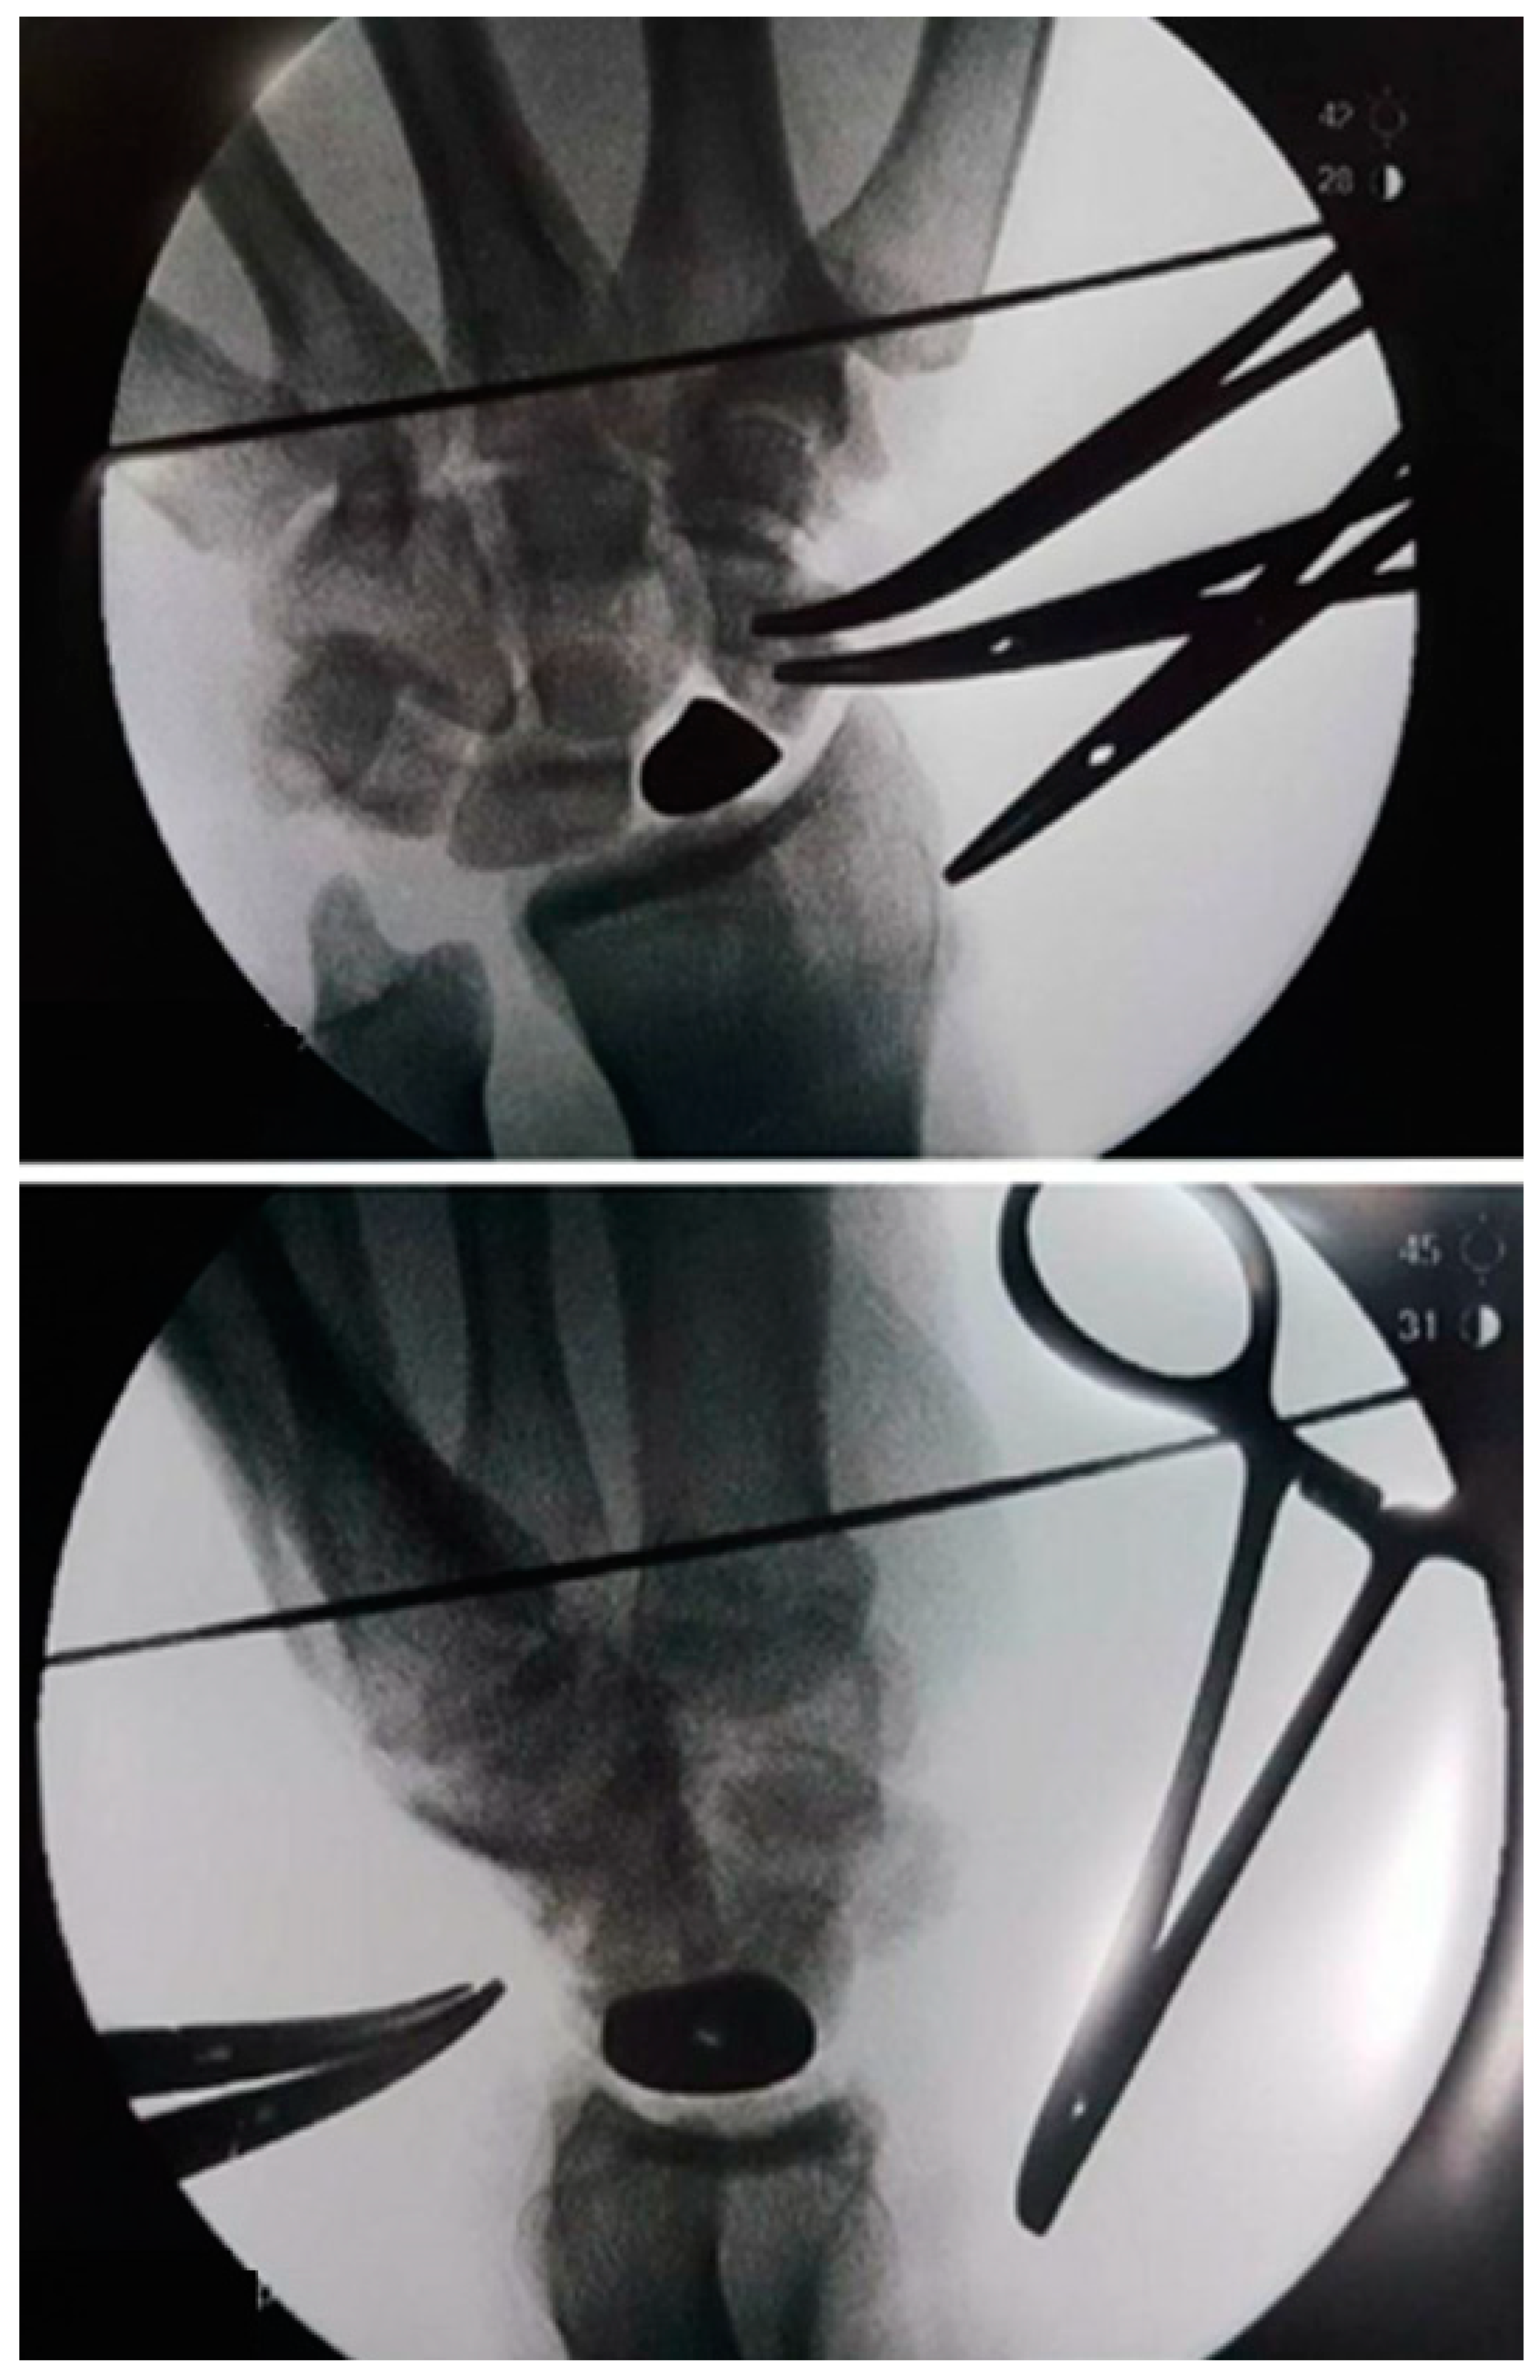

2.4. Surgical Technique